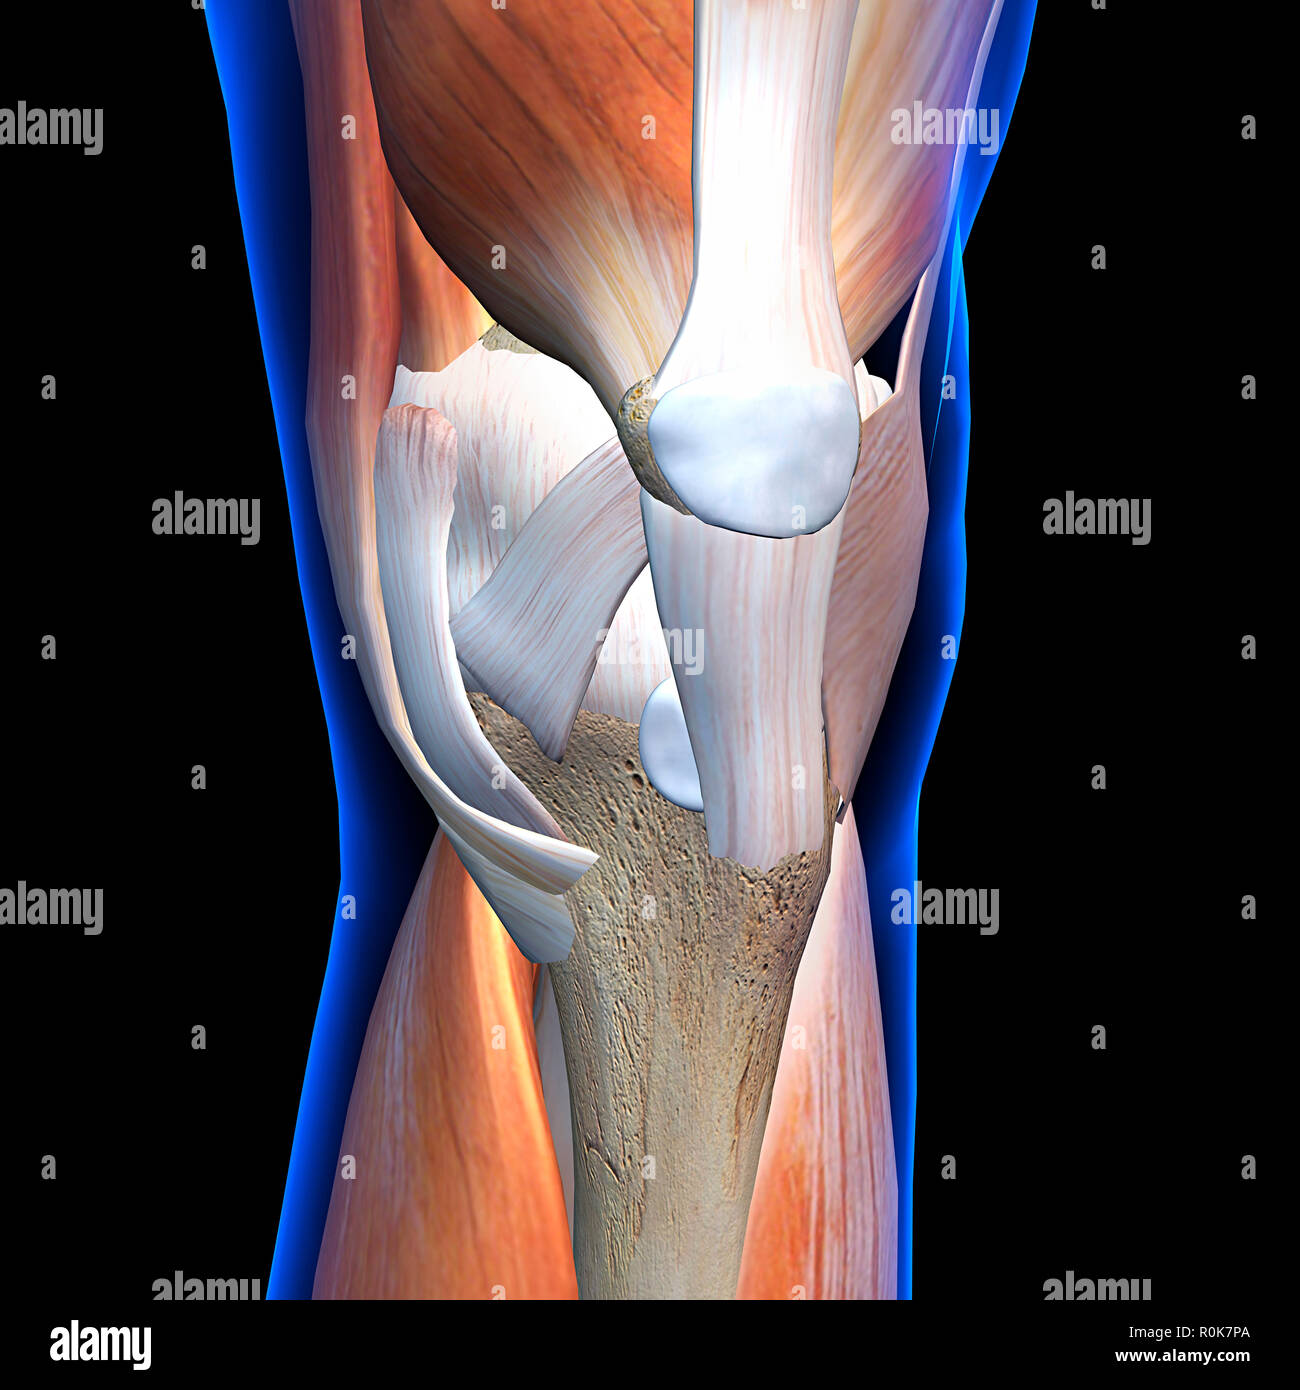

Knee joint showing muscles and ligaments with labels. Stock Photohttps://www.alamy.com/image-license-details/?v=1https://www.alamy.com/knee-joint-showing-muscles-and-ligaments-with-labels-image224157979.html

Knee joint showing muscles and ligaments with labels. Stock Photohttps://www.alamy.com/image-license-details/?v=1https://www.alamy.com/knee-joint-showing-muscles-and-ligaments-with-labels-image224157979.htmlRFR0K7P3–Knee joint showing muscles and ligaments with labels.